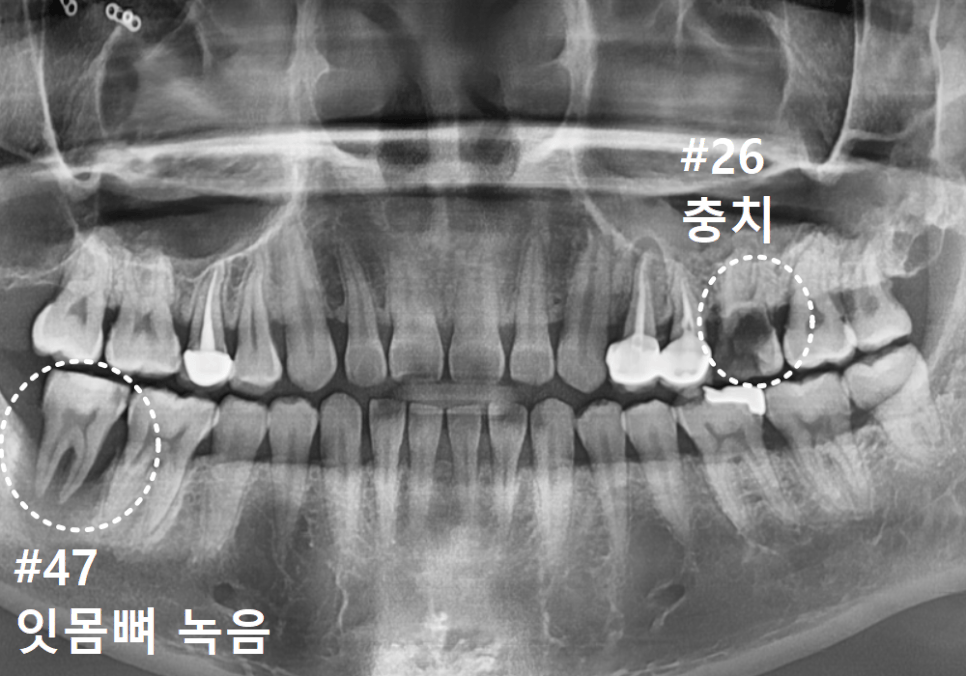

방사선 사진상으로는 상태가 더 심각했는데요.

보이는 것보다 충치가 훨씬 깊게 파고들어,

마치 겉면만 간신히 남고

속은 텅~비어버린 상태였어요.

더 주의 깊게 보아야 할 곳은

겉보기에 큰 충치가 없어 보였던

오른쪽 아래 치아였습니다.

방사선 사진을 보니 치아 주위의 뼈가

상당 부분 소실되어,

치아가 잇몸뼈 위에 불안정하게

떠 있는 상태였거든요.

이대로 두면 염증이 옆 치아까지 번져

진단 결과, 위아래 모두 치아를 살리기 어려워

발치 후 임플란트를 진행하기로 했습니다.

하지만 두 곳 모두 임플란트를 심을 뼈가 부족하여

뼈이식이 반드시 필요한 상태였는데요.